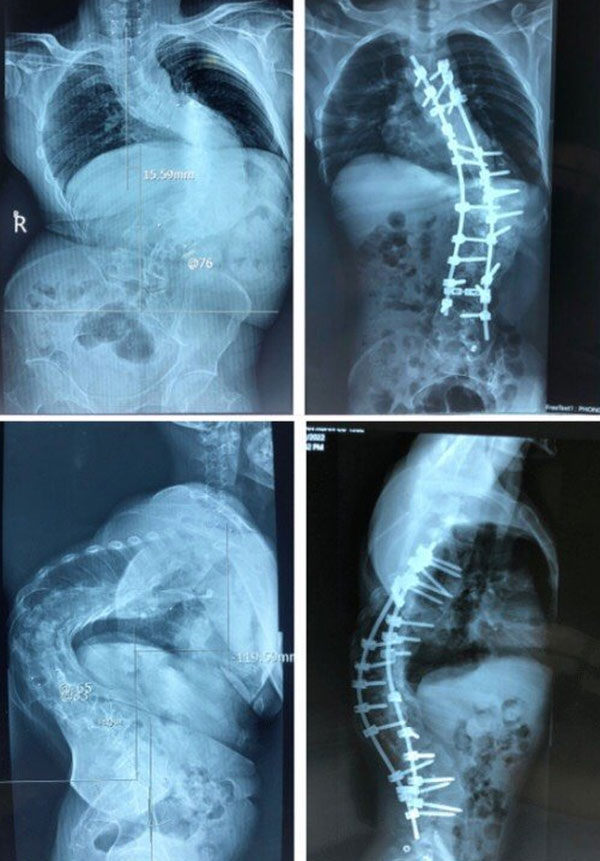

Tại Khoa Chấn thương Chỉnh hình cột sống, Bệnh viện Trung ương Quân đội 108 (Hà Nội), qua hình ảnh X-quang, tình trạng thực tế của bệnh nhân, các bác sĩ xác định đây là một ca bệnh đặc biệt khó, góc vẹo rất lớn T6L3 khoảng 126 độ. Hơn nữa, ca bệnh này càng khó khăn hơn do kèm theo gù cũng rất lớn, trên 100 độ.

Thì thứ nhất, đi lối trước, cắt xương sườn, vén phổi, cắt tối đa được 4 đĩa đệm để làm lỏng cột sống, sau đó lắp khung Halo kéo dãn trên giường nghiêng 30 độ, trong thời gian 3 tuần, với cân nặng tăng dần đến lúc đạt mức tối đa là 50% cân nặng của bệnh nhân.

Cũng bởi vì ca bệnh gù rất lớn nên các bác sĩ đã quyết định cắt V xương ở 3 mức để nắn chỉnh. Để thực hiện điều này phải là cả một sự quyết tâm lớn, bởi vì thời gian mổ dài, kỹ thuật khó, nhiều nguy cơ tai biến biến chứng. Cuộc đại phẫu cân não kéo dài nhiều tiếng.

Sau mổ, hình thể người bệnh đã gần như bình thường, chiều cao tăng thêm vài cm, bệnh nhân A. đã cảm thấy thở dễ hơn, đi lại cũng ổn hơn, và quan trọng nhất là đã tự tin hơn rất nhiều trong cuộc sống.